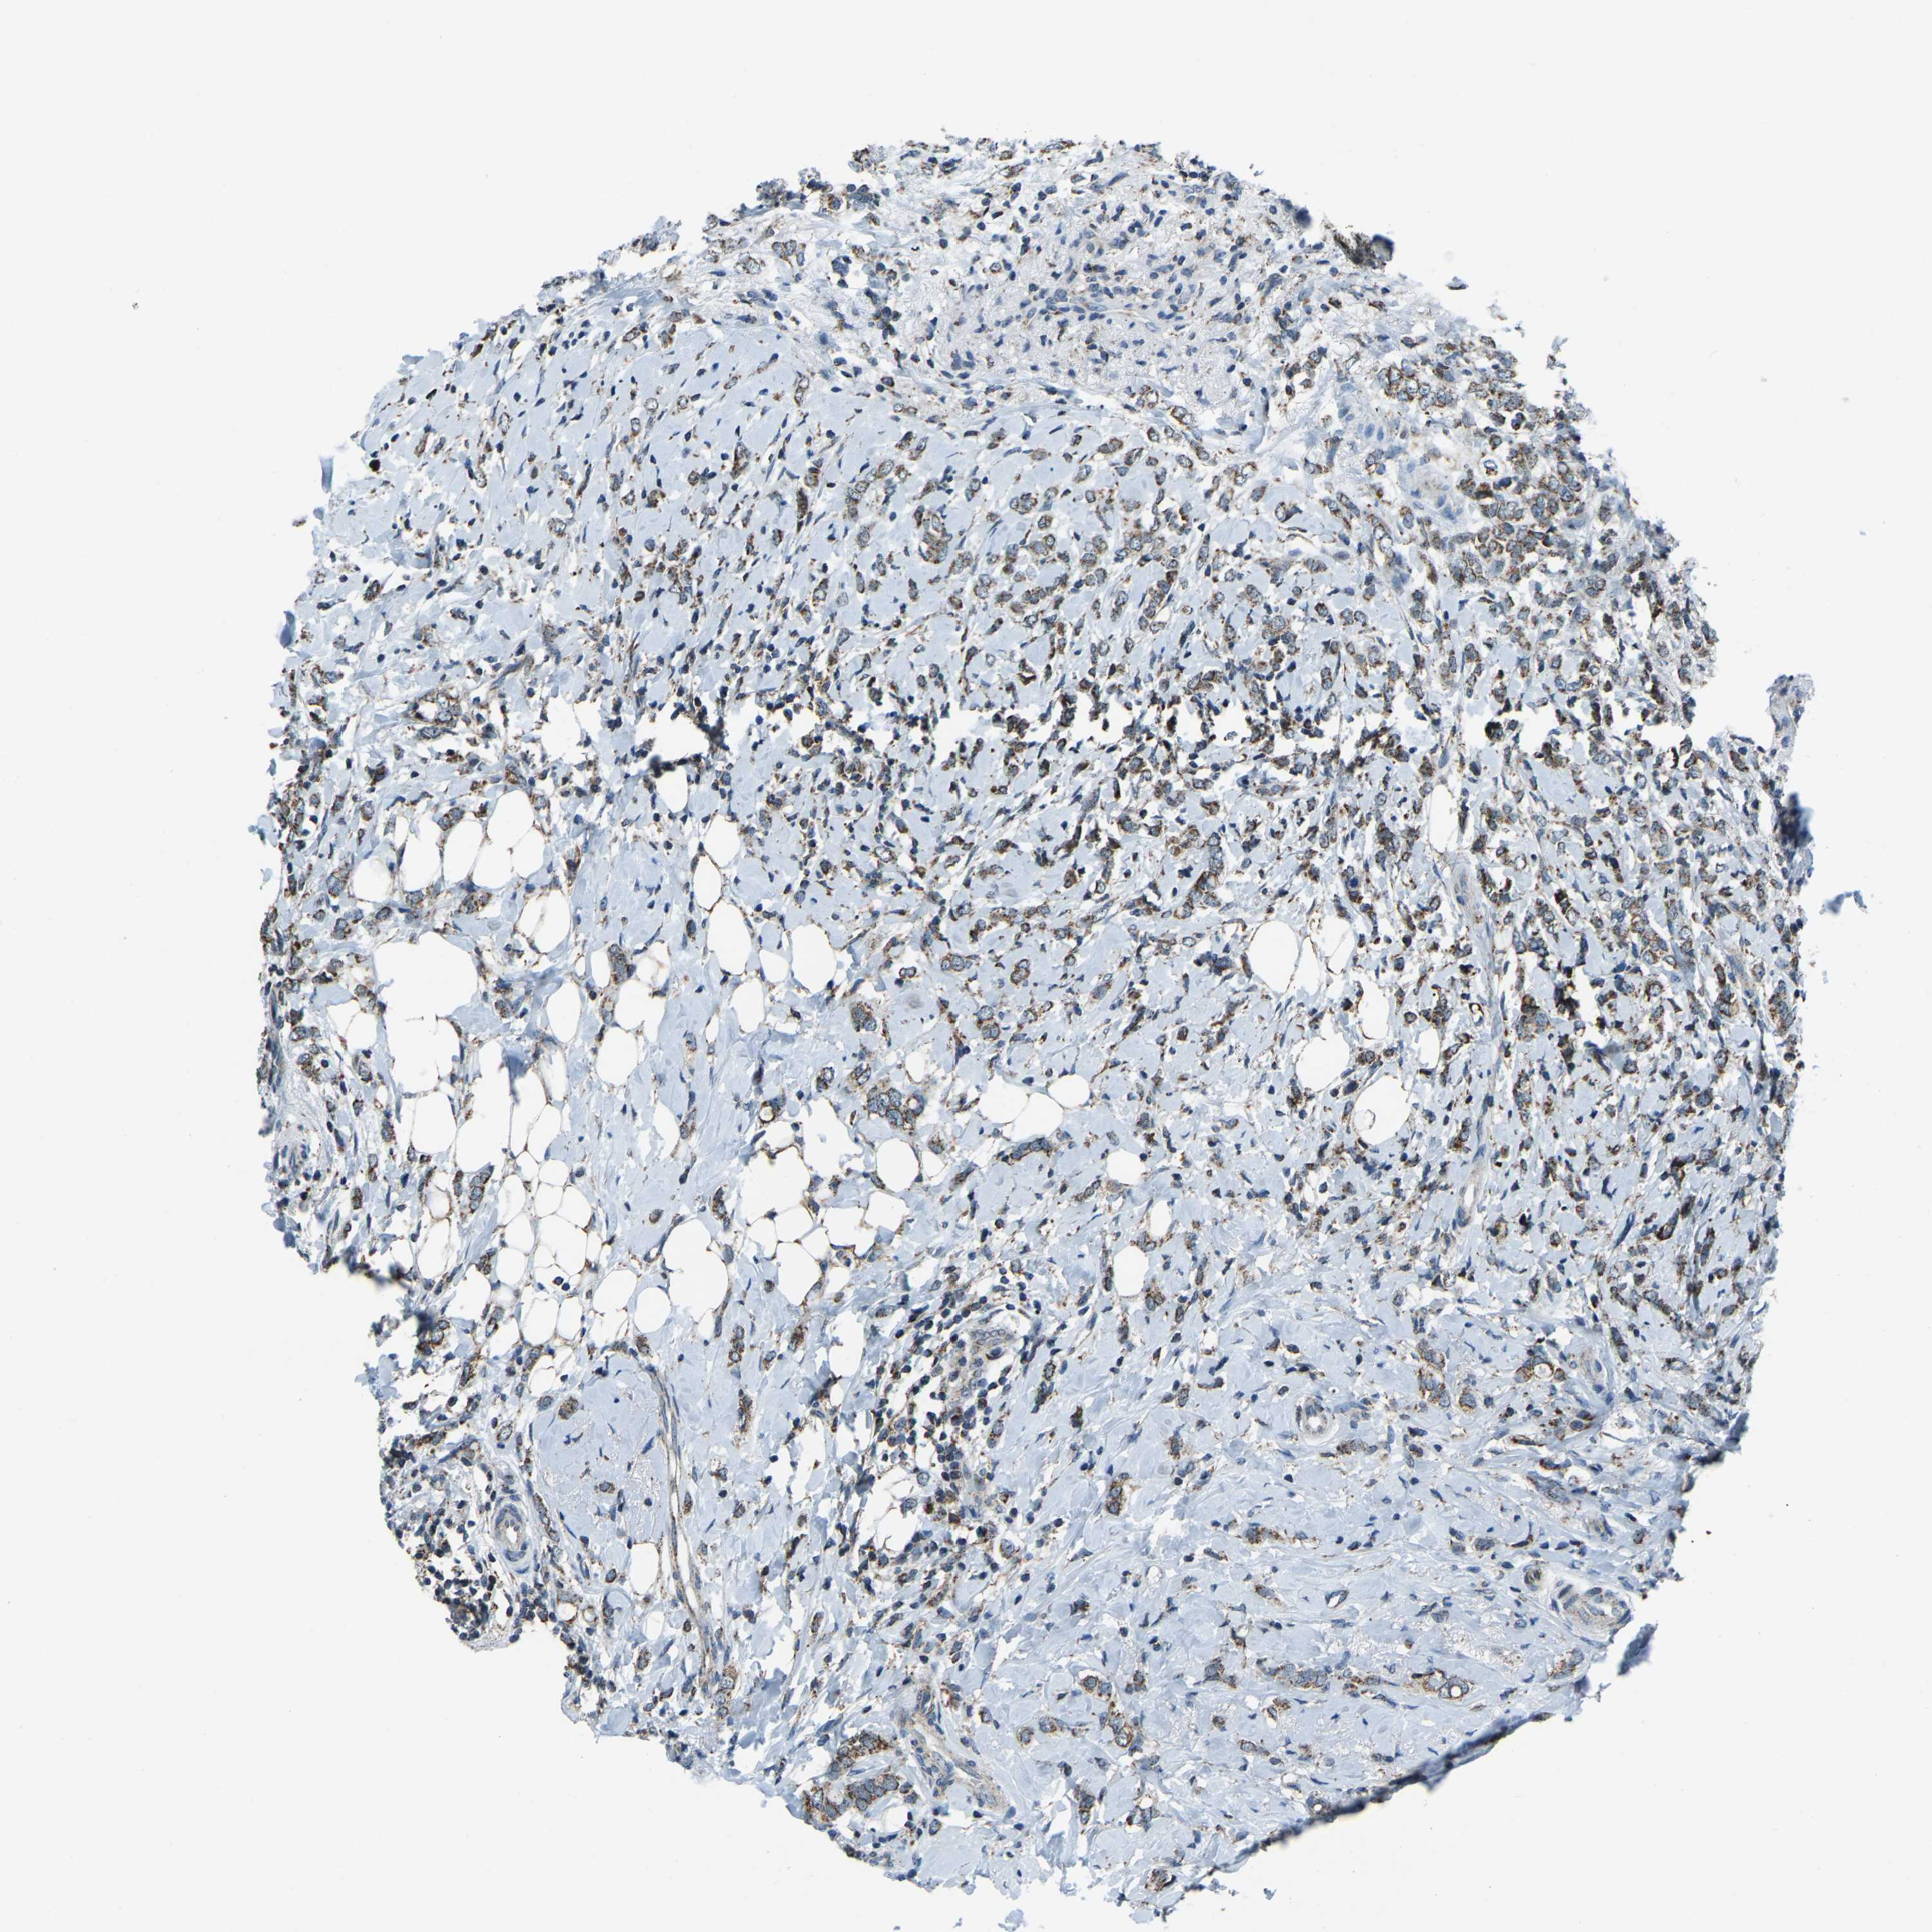

BRCA TCGA BRCA VALIDATION PROTEIN EXPRESSION